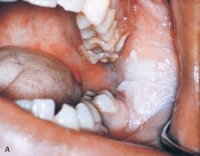

Introduction to Preliminary Diagnosis of Oral Lesions